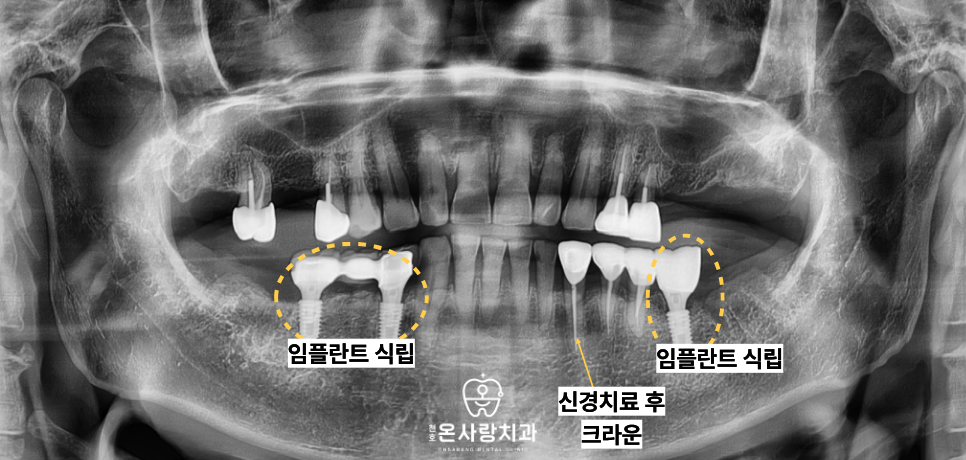

정밀 진단을 통해 하악 상태를 면밀히 분석한 결과

남아 있는 치아들의 손상 정도가 심해

정상적인 저작이 불가능하다는 판단을 내렸습니다.

대신 그 앞 단계인 6번 치아

즉, 제1대구치까지만 구치부 보철물을 제작하여

하악의 전체적인 저작 기능을

완성하는 방향으로 계획을 수립하였습니다.

치료 과정에서는 환자분이 느끼시는

하악의 통증 원인을 발치를 통해 먼저 제거하고

잇몸의 상태를 안정시키는 데 주력하였습니다.

이후 상악에 사용 중인 부분의치와의

높낮이를 맞추는 정교한 과정을 거쳤습니다.